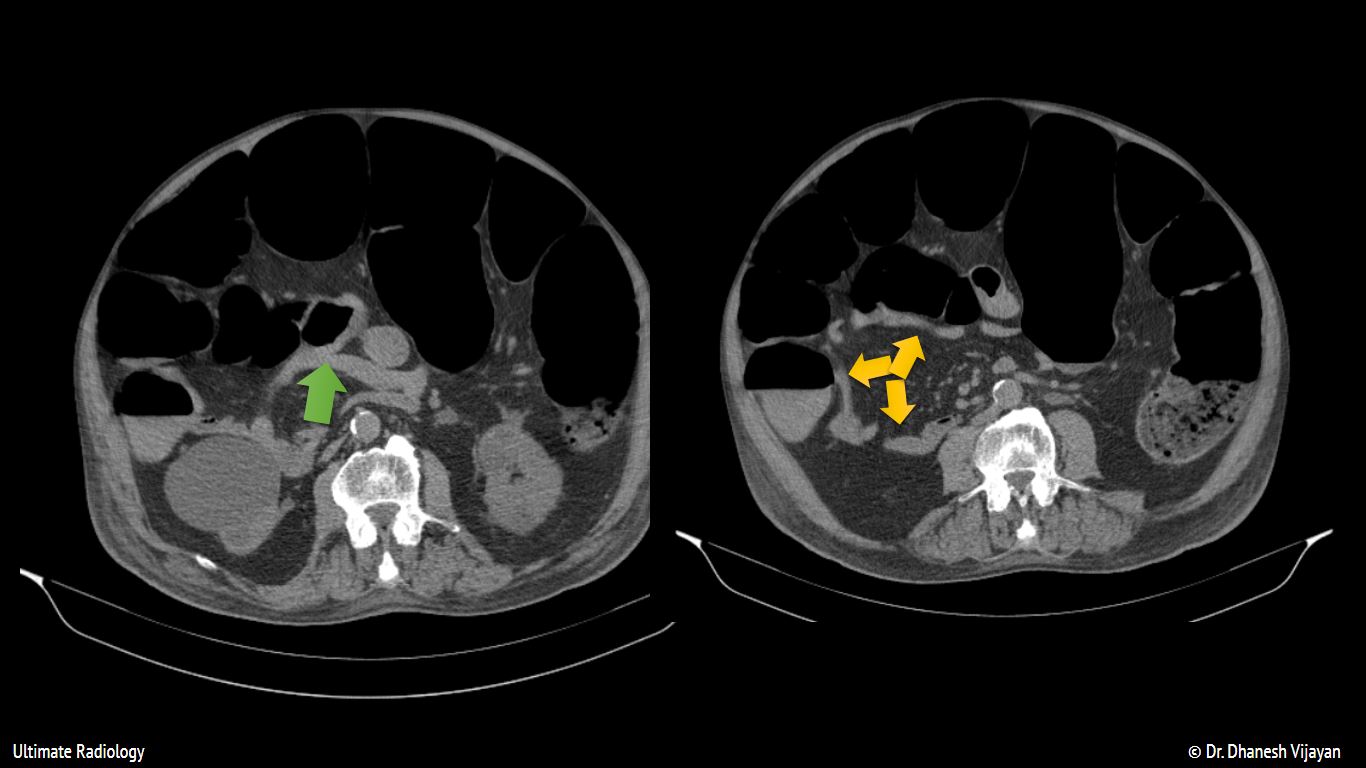

Ogilvie Bowel. In some cases the small bowel.

In some cases the small bowel.

Ogilvie Bowel In some cases the small bowel. In some cases the small bowel.